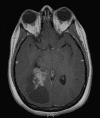

Clinical informationThe patient was a 20 year-old woman who was about 5 weeks postpartum. She presented with nausea, vomiting, and severe headache. MRI scan revealed a large cystic right ventricular tumor with extension to the right parietal occipital area but the main bulk of the tumor is within the lateral ventricle. The cystic component, however, extends to the cortical rim of the parietal occipital cortical region. Some calcifications are present. The differential diagnosis include choroid plexus tumor and intra-axial glial neoplasm. The tumor was resected and the following images are representative of the tumor.

Pathology of the Case: MRI shows a large mass with the more solid component located in the lateral ventricles and the cystic component protruding into the cortical area. The solid area is enhanced (Panel A). On low magnification, the lesion has alternating area of high and low cellularity (Panel B) with scattered calcifications in some of the sections. Medium and high magnification demonstrates perivascular coronary arrangement of cytoplasmic processes (Panel C, D, and E). The nuclei are bland and mitotic figures are not readily seen. Randomly scattered brown pigment containing cells are found in multiple areas of the tumor (Panel F, G, and H). Scant lipidized cells with enlarged nuclei (Panel I) are also present. The tumor cells are strongly positive for glial fibrillary acidic protein (GFAP) (Panel J and K) and S100 protein but are negative for epithelial membrane antigen (EMA), neurofilament proteins, and NeuN. The overall Ki67 labeling is low but focal small areas (about the size of one high power field) has increased labeling. The pigment appears to be melanin on microscopic examination. These pigments are positive with Fontana-Masson stain (Panel L) but negative for Prussian blue stain for iron (Panel M). These features confirmed that these are melanin pigments. The pigment granules are positive for periodic acid-Schiff reaction (N), negative for Ziehl-Neelsen (acid fast) stain..